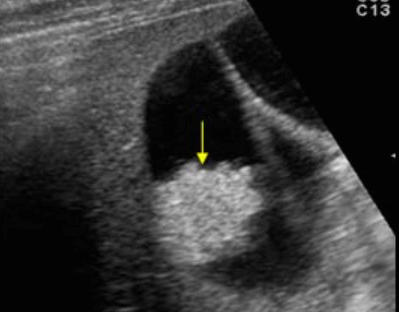

- 강한 고에코의 반사체 (strong echogenic sign)

- 후방음향음영 (posterior acoustic shadow)

- Wall-echo-shadow (WES) triad = double arc shadow sign

- 콜레스테롤 결석은 강하고 선명한 후방음영이 존재한다

- Color doppler 적용 시 twinkle artifact 가 보인다